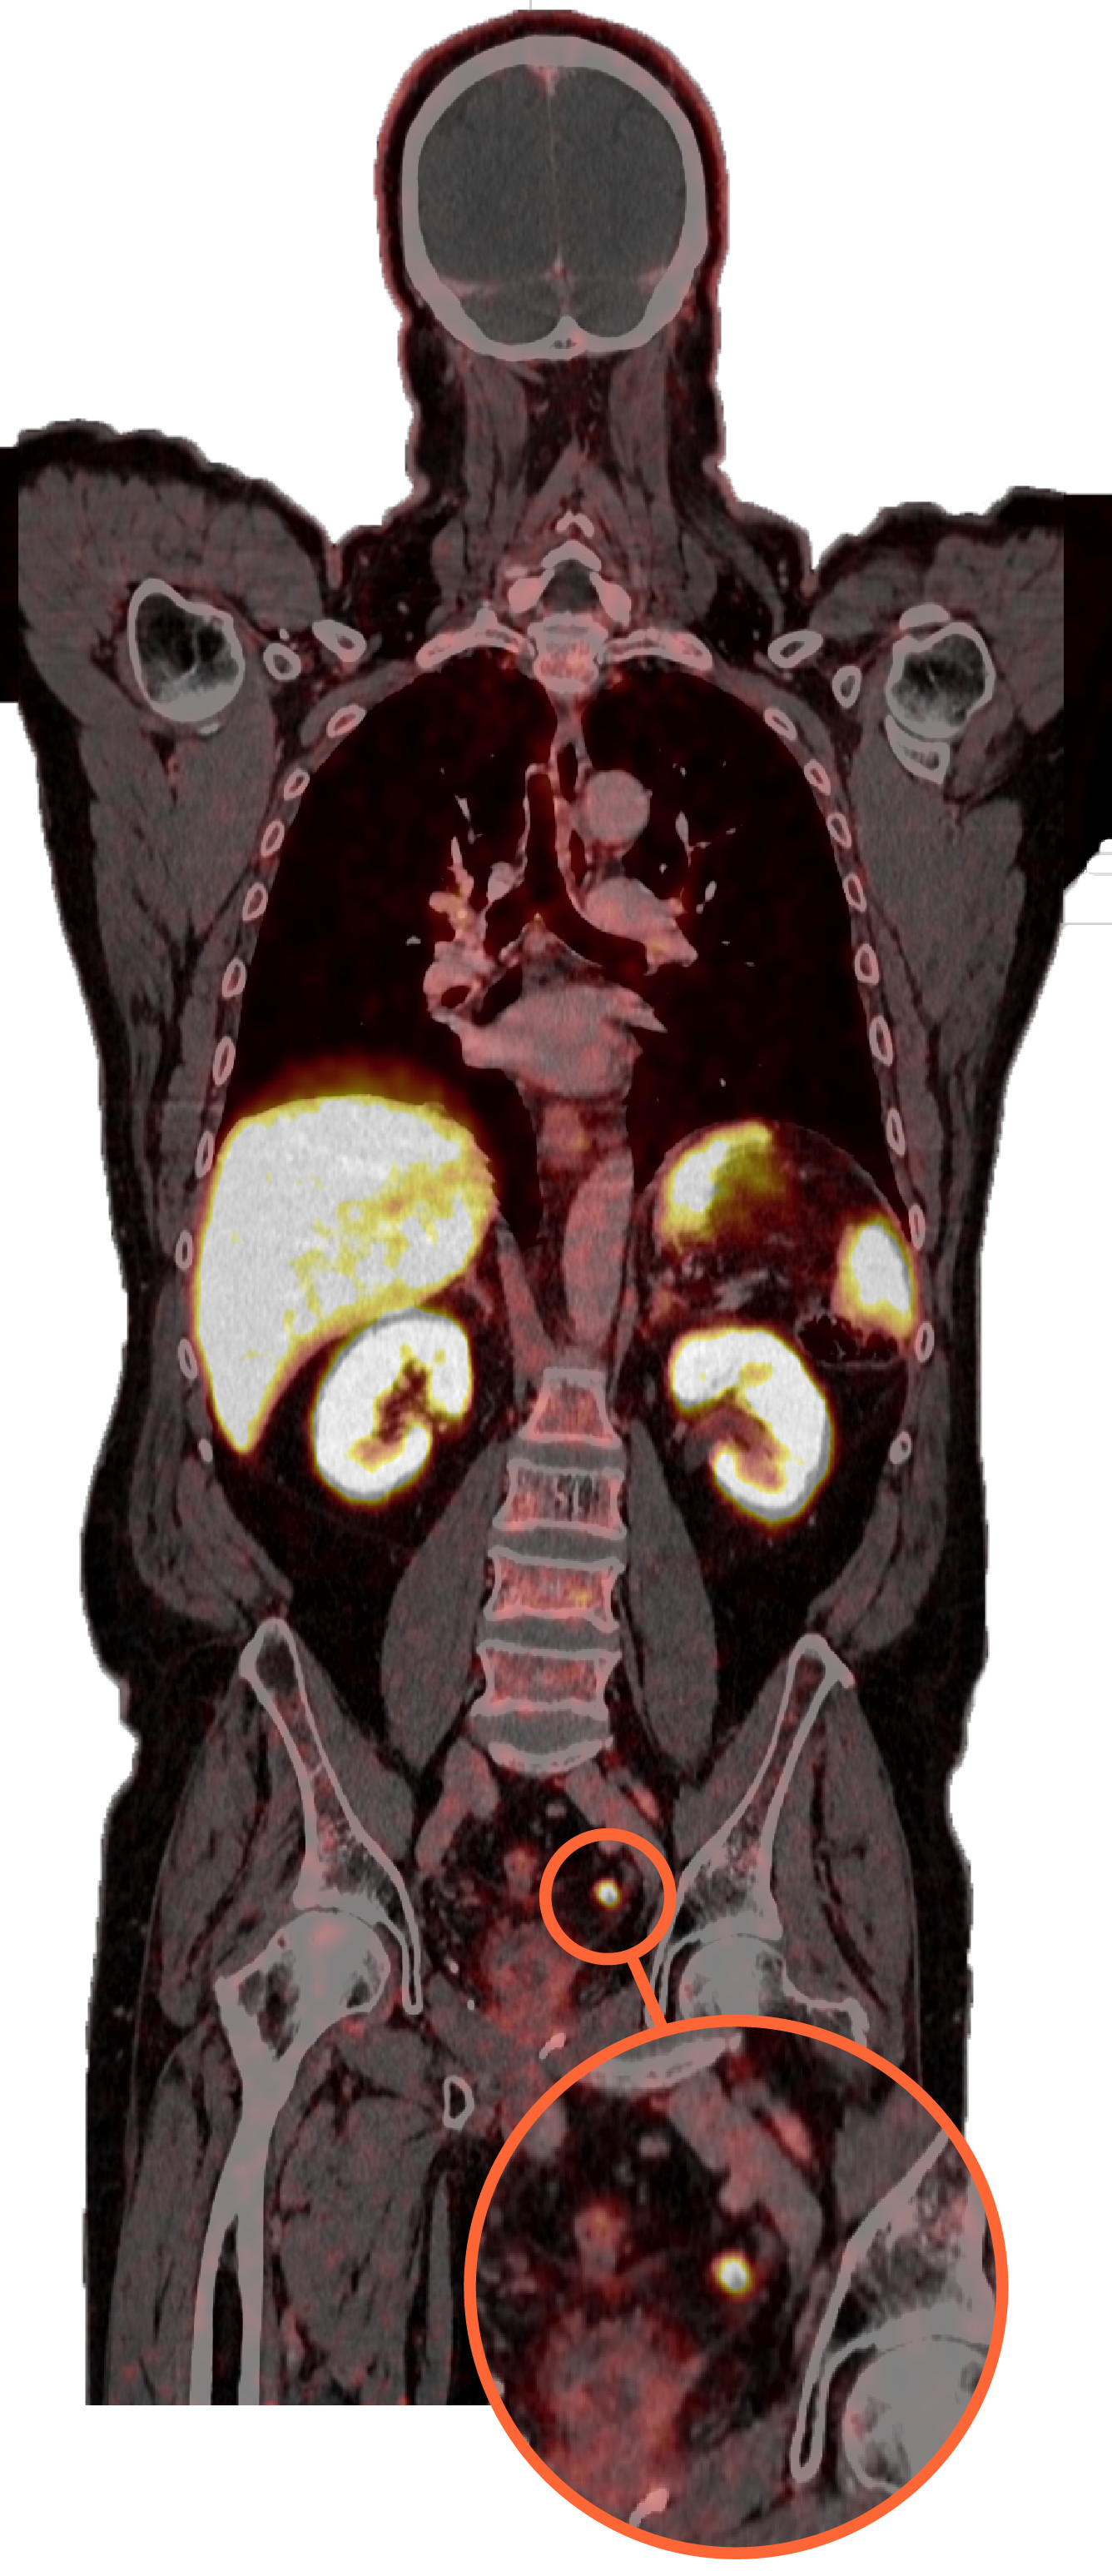

PET/TC PSMA-1007. Recidiva adenopàtica. Mil·limètrica de càncer de pròstata

En l'actualitat, els estudis PET/TC-PSMA s'han convertit en la millor eina per a la localització de la recidiva bioquímica en el càncer de pròstata.

El PSMA és una glicoproteïna transmembrana que se sobreexpressa en les cèl·lules tumorals prostàtiques. Es disposa de diversos radiofàrmacs que s'uneixen a aquesta glicoproteïna i permeten detectar les recidives del càncer d'una manera molt precoç.

Es tracta d’un radiofàrmac que permet obtenir unes imatges d’alta definició i sensibilitat per a detectar les recidives precoçment, sense interferències amb l’eliminació urinària, ja que a diferència de la resta de fàrmacs actuals, el seu metabolisme és hepàtic.